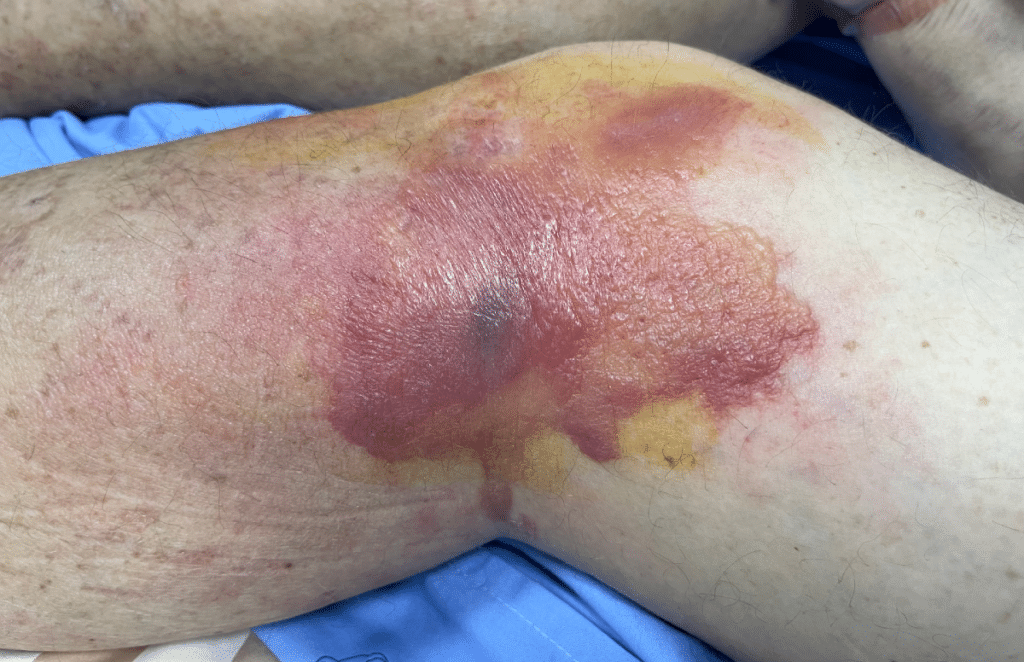

A contusion is the medical term for a bruise—a common injury that occurs when blood vessels beneath the skin are damaged by blunt force trauma, causing blood to leak into surrounding tissues. Whether from a sports injury, accidental knock, or fall, contusions affect millions of Australians each year. Understanding how to properly treat a contusion wound can significantly reduce pain and swelling, prevent complications, and speed up healing time. This comprehensive guide covers everything from recognising different types of bruises to implementing effective first aid techniques and knowing when professional medical attention is necessary.

The Physiological Process Behind Bruising

Visual Signs of a Contusion Bruise

The appearance of a bruise provides valuable information about the injury’s age and severity. Fresh contusions may appear red or purple, indicating recent blood vessel damage. Over 24 to 48 hours, the colour typically deepens to dark purple or black as blood accumulates. As healing progresses, bruises transition through green (around days 5-7) and yellow-brown (days 7-14) before fading completely. The size of the discoloured area often corresponds to injury severity—larger bruises suggest more extensive tissue damage and blood vessel rupture.